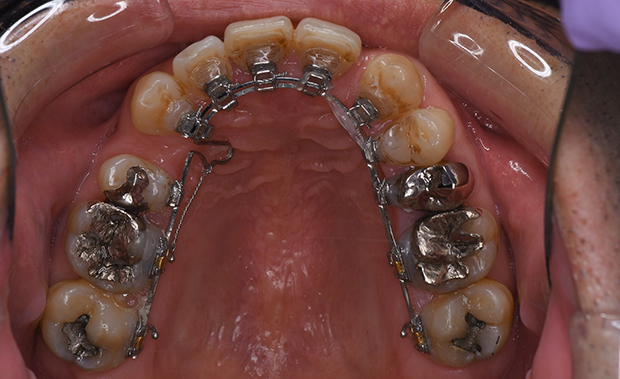

【上顎前突】叢生 抜歯 舌側マルチブラケット装置

| 主訴 |

出っ歯。ガタガタ |

||

|---|---|---|---|

| 診断名 |

High angleを伴うAngle II級叢生 |

||

| 年齢 | 14歳 | 性別 | 女子 |

| 治療に用 いた装置 |

舌側マルチブラケット装置 (セミカスタム) | 抜歯部位 | 上顎両側第一小臼歯 下顎両側第二小臼歯 |

| 治療期間 ・回数 |

2年3か月・27回 | 治療費 概算 |

約90万円 (調整料を含む) |

| 治療内容 詳細 |

中学生。上の前歯が突出していることと、ガタガタを治したいということで来院。舌側矯正(裏側矯正)希望 |

||

| リスク・ 副作用 |

装置による違和感、疼痛、歯肉炎など |

||